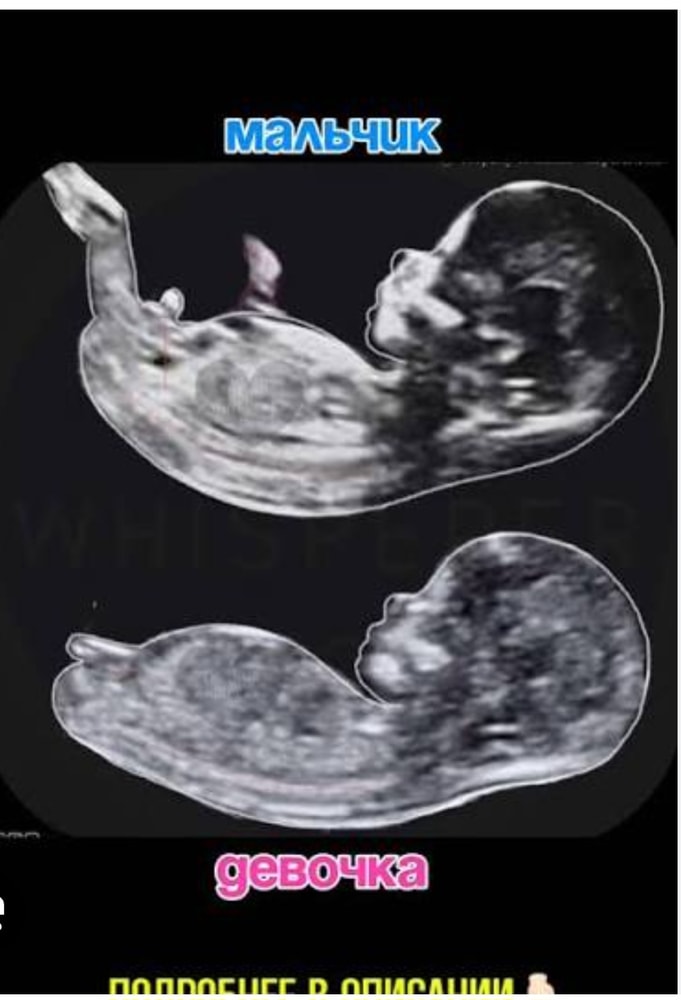

УЗИ 12 недель, половой бугорок (скриншот с видео)

Всем здравствуйте🤩 Как думаете мальчик или девочка😄?